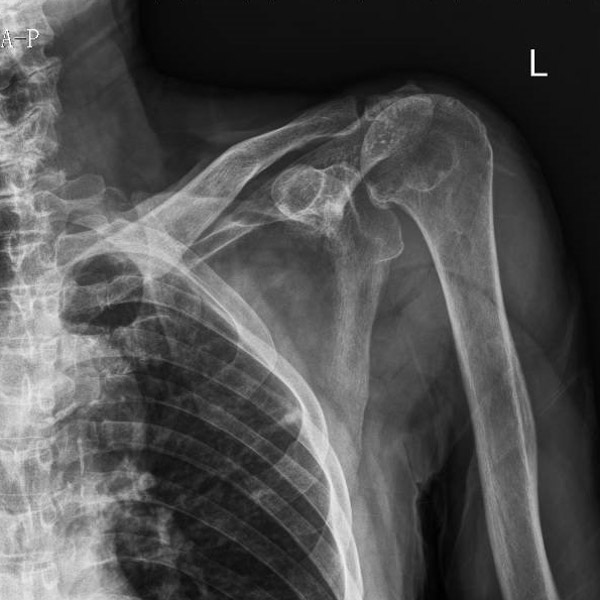

▲術(shù)前術(shù)后對比

江爺爺因車禍導(dǎo)致左肩疼痛伴活動受限,遂在家人陪同下到柳州市人民醫(yī)院創(chuàng)傷骨科就診,經(jīng)CT檢查后,發(fā)現(xiàn)患者左肩袖損傷、左側(cè)肩峰骨折、左肩關(guān)節(jié)脫位,傷情非常嚴(yán)重。

“這種情況保守治療的效果不會太好,為最大程度恢復(fù)肩關(guān)節(jié)功能,就需要為患者進行左側(cè)反向全肩關(guān)節(jié)置換手術(shù)。”創(chuàng)傷骨科副主任舒文介紹,反向全肩關(guān)節(jié)置換手術(shù)是將組成整個肩關(guān)節(jié)的肱骨頭、肩胛骨關(guān)節(jié)盂全部換成人工的,并將肱骨頭與肩胛骨關(guān)節(jié)盂位置對調(diào)——假體的“肱骨頭在上、肩胛骨關(guān)節(jié)盂在下”,和人體真正的肩關(guān)節(jié)方向相反。這是近年國際上用來治療巨大不可修復(fù)肩袖損傷等復(fù)雜肩關(guān)節(jié)疾病的最新、有效技術(shù)。